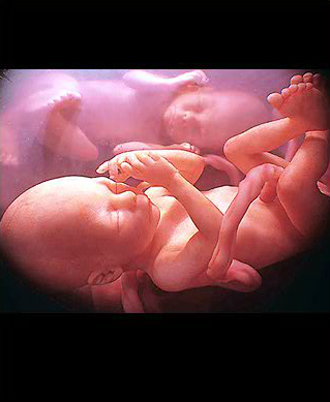

- 중기 정밀 초음파

(태아 내부장기 및 근골격 기형 등을 검사)